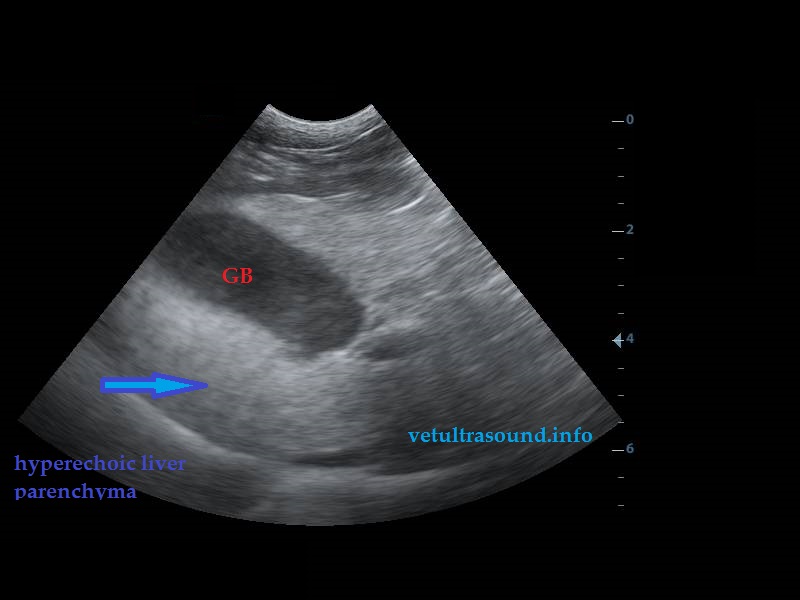

There was a mild Increase in the diameter of the caudal pole of both adrenal glands.(pic2-3)

Αύξηση των ορίων της εγκάρσιας διαμέτρου του οπίσθιου πόλου των επινεφριδίων.(pic2-3)